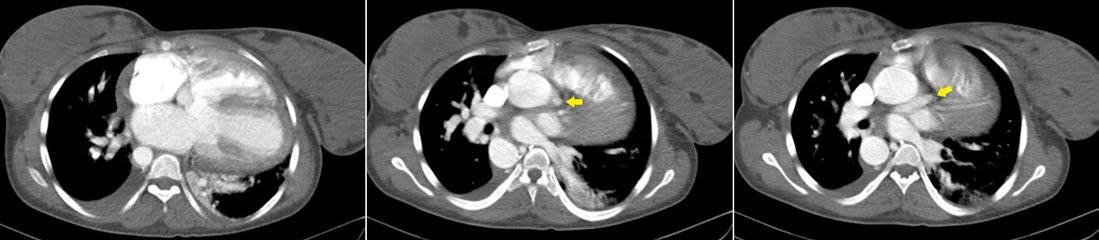

EMJ Cardiology 13.1 2025 by European Medical Journal - Issuu